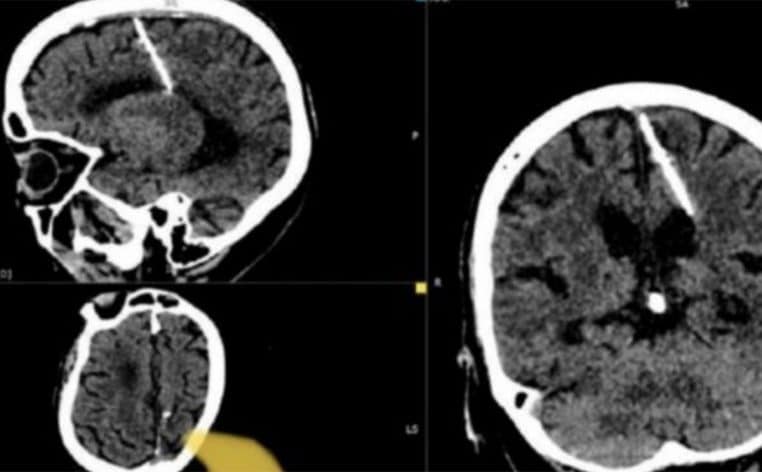

Effectivement, au cours de ses examens médicaux, l’octogénaire a découvert qu’elle vivait depuis plusieurs années avec une aiguille de trois centimètres dans le cerveau. Selon le ministère de la Santé de Sakhline, la raison de la présence de cette aiguille est simple : au cours de son enfance, elle a été victime d’une tentative d’infanticide. Toujours selon ces informations, pendant la Seconde Guerre mondiale, certains parents étaient contraints de tuer leurs nouveaux-nés pour ne pas les voir mourir de faim. Pour cela, ils inséraient une aiguille dans la fontanelle des bébés.

Après les examens, les spécialistes ont affirmé que cette aiguille ne mettait pas la vie de l’octogénaire en danger. Ils ont ainsi décidé de la laisser.